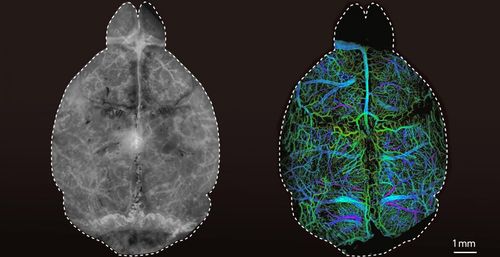

살이 있는 생쥐의 뇌를 촬영한 현미경 영상 |

이어 '양자점 대조 촉진제'가 담긴 미세방울(microdroplets)을 생쥐 모델에 투여한 뒤 DOLI 기술을 적용해, 방울 하나하나의 뇌 속 위치를 확인하는 데 성공했다.

라찬슈키 교수는 "수술 등을 하지 않는, 완전히 비침습적인(noninvasive) 방법으로 산 생쥐의 깊은 뇌 속 미세혈관과 혈액 순환을 고해상도로 시각화한 건 처음"이라고 강조했다.

연구팀은 얼마나 깊은 위치에 있는지에 따라 시각화한 미세방울의 크기가 달라진다는 것도 확인했다. 이는 DOLI 기술로 입체 영상도 구할 수 있다는 걸 의미한다.